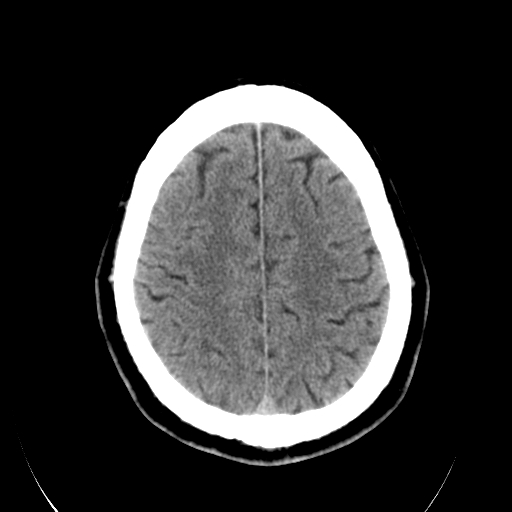

标题: CT28335:男,58岁,请各位看看是不是有脑积水,蝶窦内高密 [打印本页]

标题: CT28335:男,58岁,请各位看看是不是有脑积水,蝶窦内高密

轻度积水,蝶窦正常。

脑积水!建议行mri!

1)脑积水。2)副鼻窦炎。